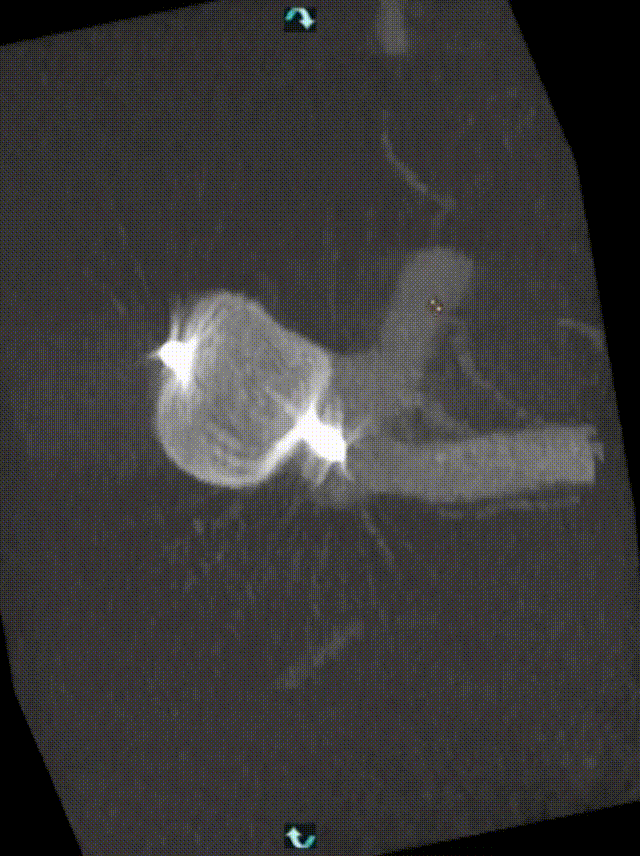

造影提示:基底动脉末端动脉瘤,囊状,形态规则,大小约7.4*7.2mm,瘤颈宽4.4mm。

动脉瘤宽7.6mm,高5.97mm

动脉瘤宽8.12mm,高4.97mm

动脉瘤宽6.6mm,高4.8mm

动脉瘤宽7.9mm,高4.8mm

经测量后充分评估,选用瘤内扰流装置WEB™ SL 9*4mm进行动脉瘤栓塞治疗。

造影,确认WEB™在动脉瘤瘤内位置,确认WEB™受到侧向挤压力,贴紧瘤壁,WEB™内造影剂滞留。WEB™近端局部突出于左侧P1段,需重新调整WEB™形态。

多次回收WEB™至开花,调整WEB™位置及形态,造影后见双侧大脑后动脉显影良好无明显狭窄。

解脱后,多角度复查造影,可见WEB™内造影剂滞留,分支血管及载瘤动脉血流正常,手术顺利,行即刻Xper-CT颅内未见出血。